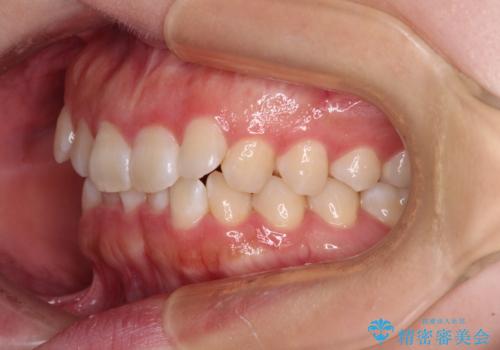

前歯のデコボコを整える インビザラインによる矯正治療

- 上下前歯のデコボコを気にして来院された患者様です。

叢生は軽度であり、ワイヤー矯正でもマウスピース矯正でも対応可能であったので、好きな装置を選んでもらいました。

相談の結果、インビザラインによる矯正治療を行うこととしました。

毎日の装着時間をしっかりと守っていただいたことで、1年程度で無事に治療を終えることができました。